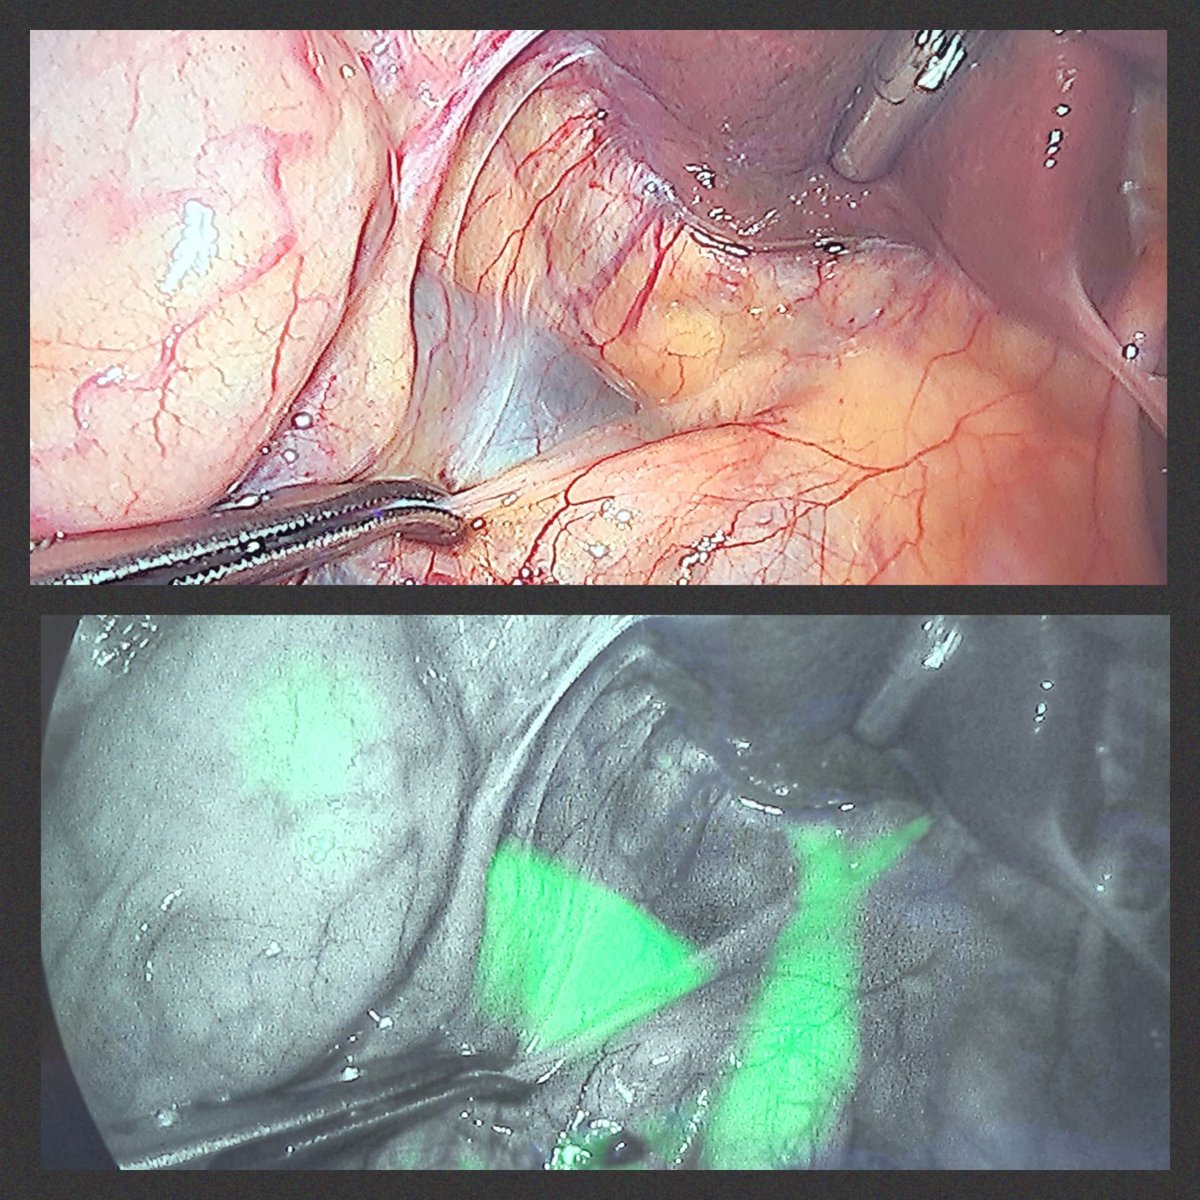

#ICG for #incisionlesscholangiography during #LC allows early visualisation of the Biliary tree not seen under white light. See the #CBD, right and left #HD, at the #hilum shining 🟩. #some4HPB #SoMe4Surgery